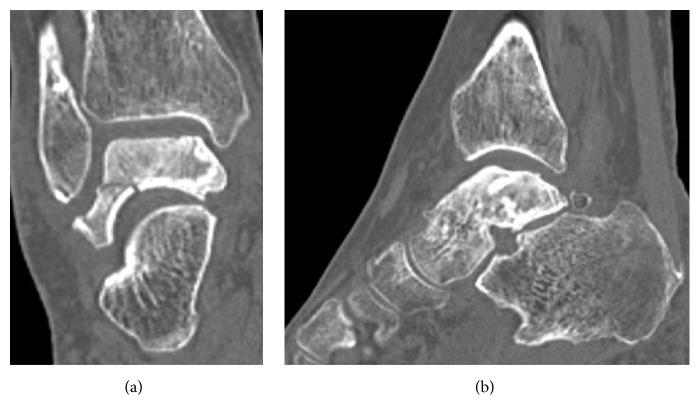

Two women aged 65 years and 78 years presented to our center with idiopathic necrosis of the talus. In both cases, imaging examinations showed collapse and sclerotic changes of the talar body caused by the necrosis. Both women underwent resection and placement of a third-generation custom-made alumina ceramic total talar prosthesis. Immobilization of the ankle in a short-leg cast for 3 weeks was followed by early rehabilitation. One year and 6 months after surgery, both women were able to walk without pain. Their Japanese Society for Surgery of the Foot ankle-hindfoot scale scores improved from 22 and 29/100 points to 90 and 95/100 points, respectively. To the best of our knowledge, the successful treatments of these two rare cases of idiopathic necrosis of the talus are among only a few reported cases of using a third-generation alumina ceramic prosthesis.

两名年龄分别为65岁和78岁的女性因距骨特发性坏死前来我院就诊。在这两个病例中,影像学检查均显示坏死导致距骨体塌陷和硬化改变。两名女性均接受了第三代定制氧化铝陶瓷全距骨假体的切除和植入手术。踝关节用短腿石膏固定3周后进行早期康复治疗。术后1年零6个月,两名女性均能无痛行走。她们的日本足踝-后足外科学会评分分别从22分和29/100分提高到90分和95/100分。据我们所知,这两例罕见的距骨特发性坏死的成功治疗是仅有的几例使用第三代氧化铝陶瓷假体的报道病例。